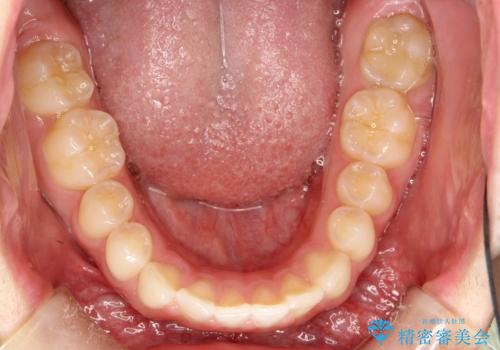

前歯の隙間がきになる インビザラインですきっ歯の治療

- 上の前歯の隙間を主訴に来院されました。

正中に隙間があり、かみ合わせが深い過蓋咬合という状態でした。

インビザラインにて矯正治療を行いました。